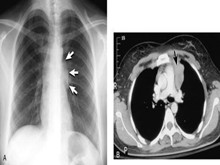

胸腺瘤

确定